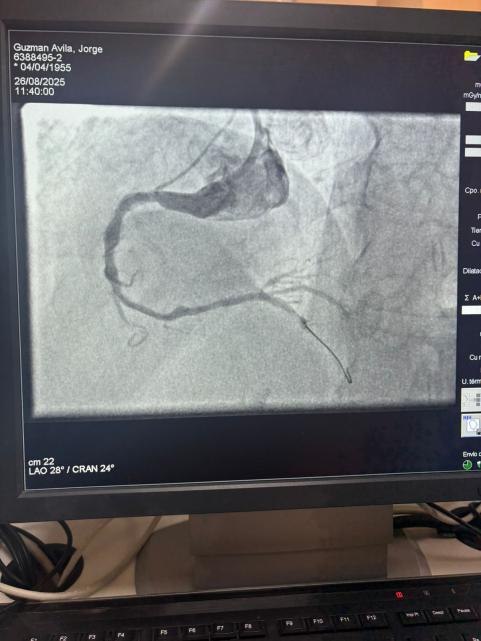

Jesteśmy dumni, że możemy podzielić się niezwykłym przypadkiem ze Szpitala Sótero del Río w Chile, gdzie dr Martín Valdebenito z powodzeniem leczył silnie zwapnione uszkodzenie w prawej tętnicy wieńcowej (pierwsza krzywa) za pomocą naszego systemu cewnika Vesscrack Coronary IVL Balloon Dilatation.

Procedura osiągnęła znakomite wyniki, przy czym zwapniały obszar skutecznie pękł i przywrócono przepływ w naczyniu. To kolejny kamień milowy w rozszerzaniu globalnego dostępu do zaawansowanych rozwiązań dla złożonych zwapnień wieńcowych.

Porównanie obrazów angiograficznych przed zabiegiem i po zabiegu wyraźnie pokazuje znaczący wpływ kliniczny naszej technologii IVL.